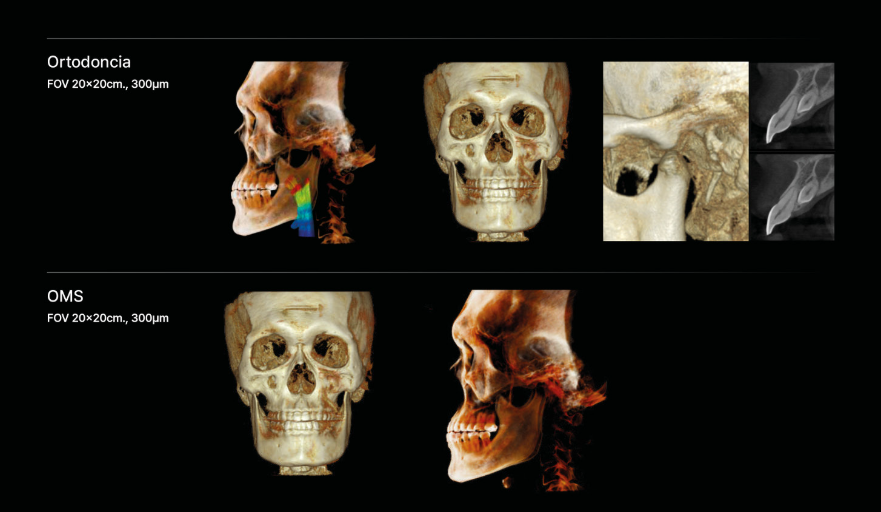

Para Ortodoncia y OMS

El tratamiento con FOV libre, proporciona múltiples posibilidades

Aborde Más Odontología

- Ortodoncia

- Planificación de implantes All on X

- Reconstrucción facial

- Cirugía Ortognática

- Traumas

- Análisis de senos nasales y vías respiratorias

- Implantología

- Endodoncia

- ATM Dual

- Impactos complejos

Imágenes de alta resolución para un diagnóstico preciso

Experimente una claridad de imagen excepcional y volúmenes de escaneo personalizables con RAYSCAN S. Adapte sus exploraciones para satisfacer sus necesidades clínicas específicas, asegurándose de capturar cada detalle intrincado y liberando posibilidades ilimitadas.

Diágnostico de todas las áreas